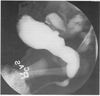

5-day-old boy has vomiting and dehydration. His serum C02 is 12 mEq/L, K+ 5.5 mEq/L, and creatinine 2.2 mg/dl. A VCUG demonstrates PUV and bilateral grade 4 VUR. The next step is:

D

The management of the infant with a PUV depends on the severity of the obstruction and the degree of any rena l dysplasia present. The main problems a rise in management of the infant with severe obstruction and compromised rena l function with dehydration, acidosis, and sepsis. Initially, a sma ll infant feeding tube, placed transurethra lly, can provide bladder drainage. Once stabilized, valve ablation can be undertaken. Vesicostomy is reserved for infants who cannot undergo primary va lve ablation because of the inadequate size of their urethra or for very small, unstable infants. If initial bladder level drainage does not result in satisfactory clinical improvement, temporary supravesical diversion may be considered; however, the vast majority of these patients will be found to have rena l dysplasia, not ureterovesica l obstr uction, as the etiology of the persistently elevated creatinine.